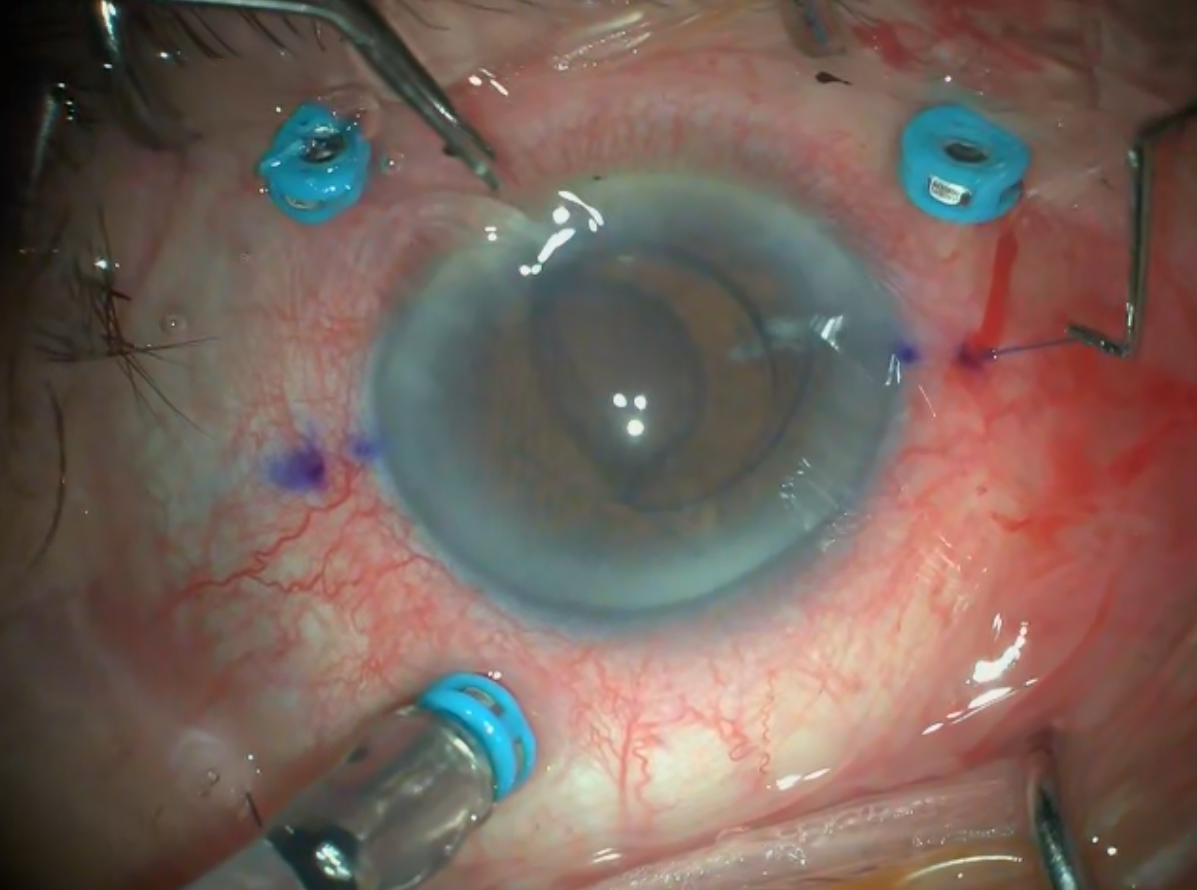

Retina dekolmanı cerrahisi sırasında perflorokarbon sıvı uygulaması esnasında ge ...